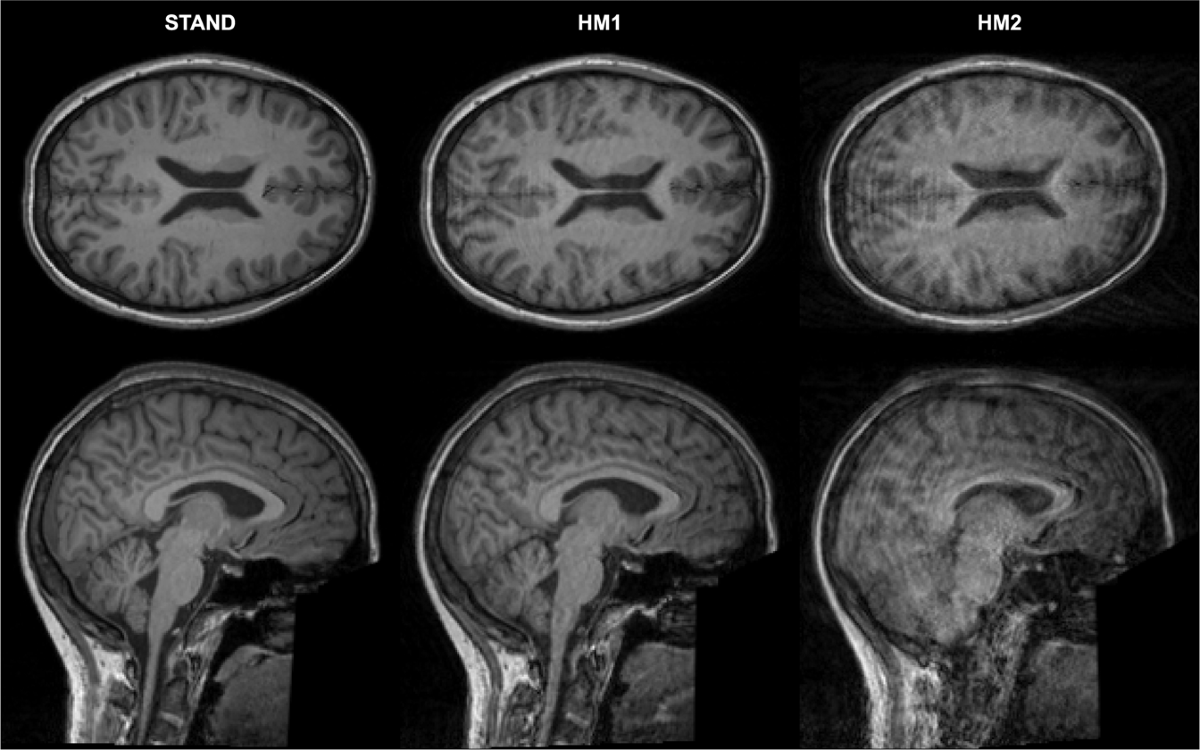

Motion Related MRI Artifacts

Movement-related artifacts are among the most common. These include ghosting, blurring, or repeated patterns in the image. Patients are often asked to stay very still during scans to reduce these problems. In some cases, sedation may be used for children or patients who cannot remain still. Using fast imaging techniques can also help reduce motion artifacts while maintaining clear images.